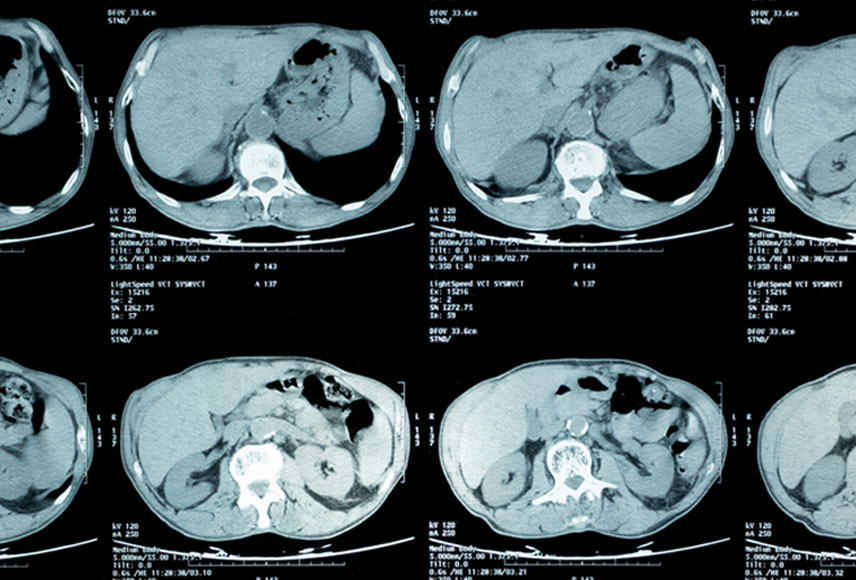

Der Quantitative Imaging Workshop (QIW) bringt führende Experten aus der ganzen Welt zusammen, um die Entwicklung von Biomarkern für die quantitative Niedrigdosis-Computertomographie (LDCT) zur Erkennung und Behandlung früher Thoraxerkrankungen – Lungenkrebs, COPD und Herz-Kreislauf-Erkrankungen – voranzutreiben. Diese drei sind die vier häufigsten Todesursachen in den USA.

Der Workshop, der von der Prevent Cancer Foundation in Zusammenarbeit mit der American Lung Association veranstaltet wird, ist ein hochkarätiges, multidisziplinäres Forum, in dem die Teilnehmer spannende neue biomedizinische Möglichkeiten erkunden, die sich durch den Einsatz dieser bahnbrechenden Bildgebungstechnologien ergeben. Die Teilnehmer kommen aus der Industrie, der Wissenschaft, Berufsverbänden, der Regierung und von Patientenverbänden und kommen zusammen, um Fortschritte zu diskutieren und Empfehlungen für die nächsten Schritte in der Thoraxbildgebung abzugeben. Learn more about this year’s workshop.